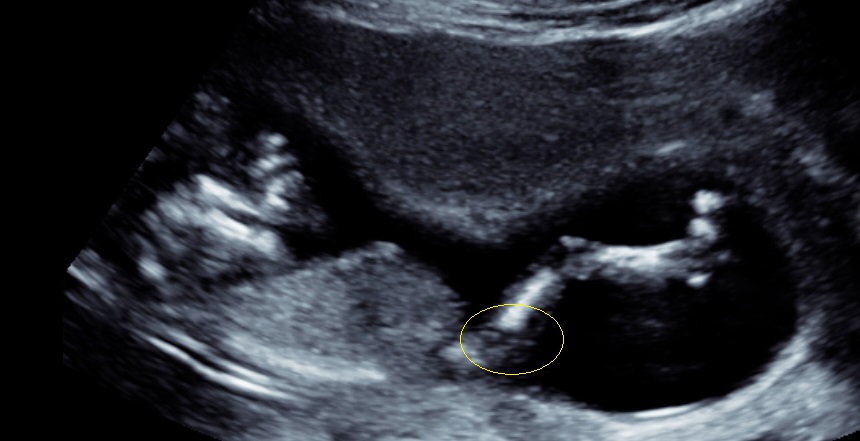

Here are a couple of pics from my ultrasound at 12 weeks 4 days... What do you think? I have a gut feeling it's a girl, but as long as it stays healthy all is good :) xo

Thank you! Here is a side on of hers/his legs... maybe this will help?Attachment 39223